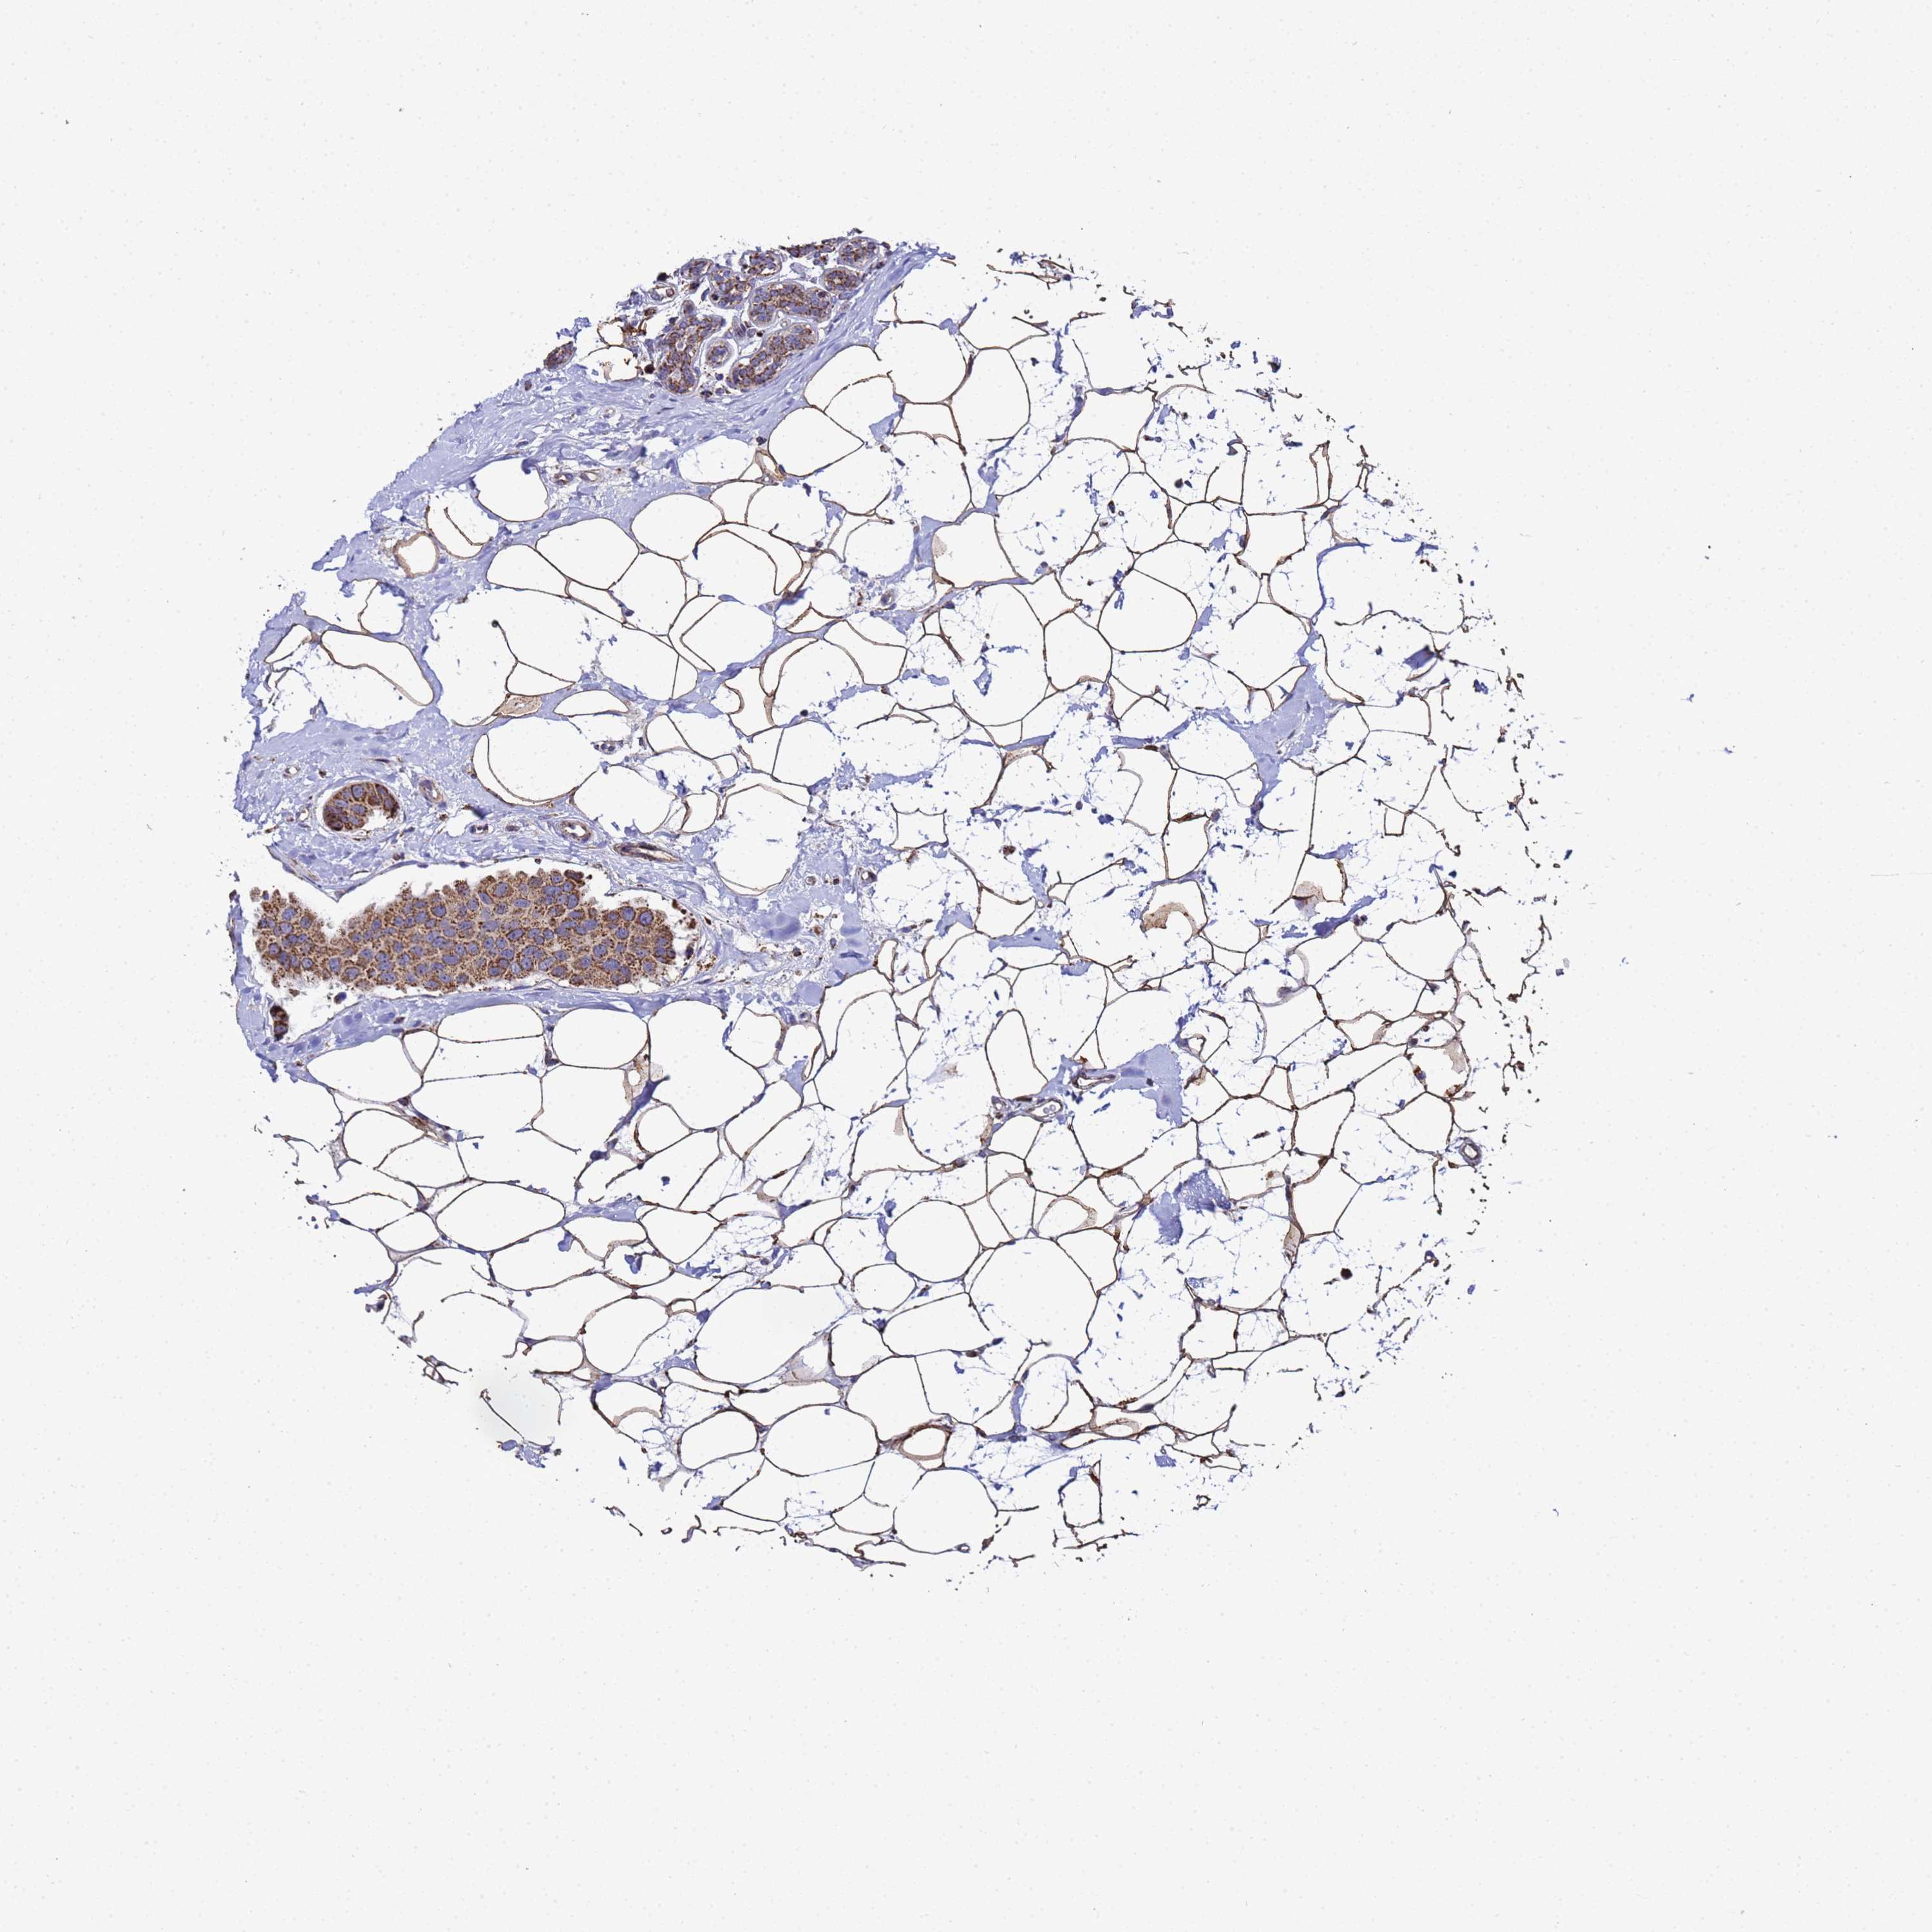

CANCER BREAST CANCER Show tissue menu

BRCA TCGA BRCA VALIDATION PROTEIN EXPRESSION

ANTIBODIES

AND

VALIDATION